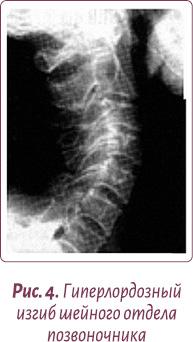

Чаще всего этот физиологический изгиб гипертрофируется, и шейные позвонки «проваливаются» вглубь шеи — формируется гиперлордоз шейного отдела позвоночника, зажимая нервные окончания и перекрывая кровоснабжение мозга (рис. 4, 5).